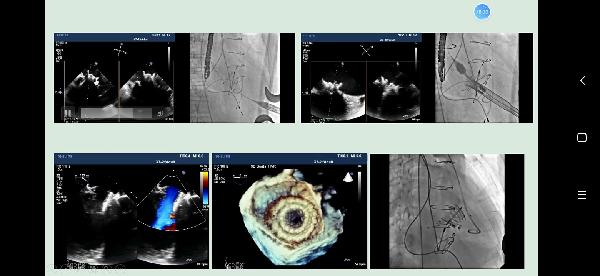

超声医学发展速度日新月异,它是影像医学的重要组成部分,也是医学影像学专业最重要的专业课程之一。孟欣副教授从心脏瓣膜的定义及解剖,心脏瓣膜的功能,正常瓣膜的超声表现,常见瓣膜病类型及超声表现四个方面结合精美的视频动画和生动的临床病例,深入浅出的让学生对瓣膜病有了进一步的了解和认识。同学们对孟欣教授所讲授的瓣膜病知识内容表现出了浓厚的兴趣,在线上交流环节,孟欣副教授一一解答了师生的提问,最后鼓励大家认真学好专业知识,提高自身专业素养。